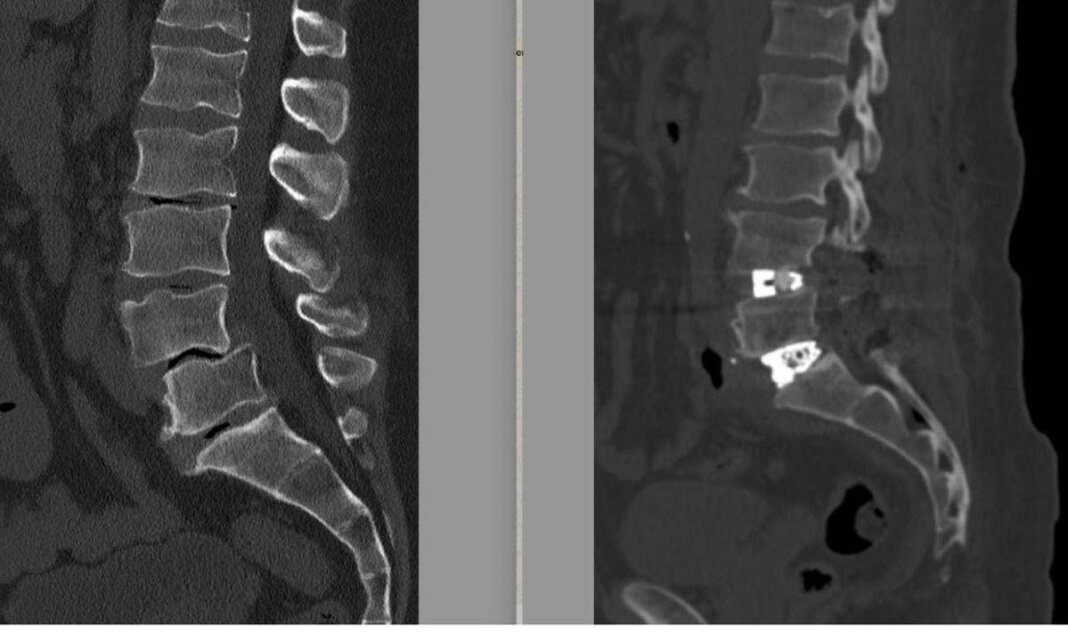

La diagnosi era di spondilolistesi tra la quarta e la quinta vertebra lombare (L4-L5), una patologia degenerativa cronica caratterizzata dallo scivolamento progressivo di una vertebra sull’altra, associata a una discopatia del disco intervertebrale L5-S1. Nel tempo – sottolineano gli esperti – questa deformità determinava una compressione significativa delle radici nervose, provocando una sciatalgia bilaterale invalidante, con dolore irradiato agli arti inferiori che peggiorava in posizione eretta e durante le attività quotidiane e lavorative, compromettendo in modo rilevante la qualità di vita.

Un passaggio fondamentale nella pianificazione dell’intervento chirurgico – illustra la nota – è stato lo studio dei cosiddetti ‘parametri spino-pelvici’, effettuato su una radiografia dell’intera colonna vertebrale. Questi supportano il chirurgo vertebrale nella scelta dell’approccio chirurgico più corretto e della tipologia di impianti da utilizzare in base al grado di lordosi da ripristinare. “Oggi la chirurgia vertebrale non si limita a liberare i nervi o a stabilizzare un segmento ritenuto instabile – precisa il neurochirurgo e chirurgo vertebrale – ma punta a ricostruire un assetto posturale il più possibile fisiologico. Il mancato rispetto e, quando possibile, ripristino di questi parametri può portare nel tempo al fallimento del costrutto impiantato nella colonna vertebrale o alla prematura degenerazione dei segmenti della colonna adiacenti a quello trattato”.

L’intervento è stato eseguito all’inizio di febbraio 2026 ed è durato circa 6 ore, riferiscono i sanitari. A 12 ore dalla chirurgia è stata eseguita una Tac addominale senza mezzo di contrasto per escludere eventuali complicanze legate all’accesso anteriore, mentre una radiografia in posizione eretta ha consentito di verificare immediatamente la qualità della correzione ottenuta. Il decorso post-operatorio è stato regolare. Il paziente si è risvegliato con un miglioramento sostanziale della sintomatologia sciatalgica e con un dolore limitato alle ferite chirurgiche, gestibile con comuni analgesici. In assenza di complicanze neurologiche o generali, è stato dimesso in seconda giornata post-operatoria. Rientrato a casa, il paziente prosegue il monitoraggio clinico con l’équipe di Chirurgia vertebrale di Tiberia Hospital. Nelle prime settimane, la riabilitazione consiste principalmente nella deambulazione e nella ripresa graduale delle attività quotidiane senza caricare la colonna.